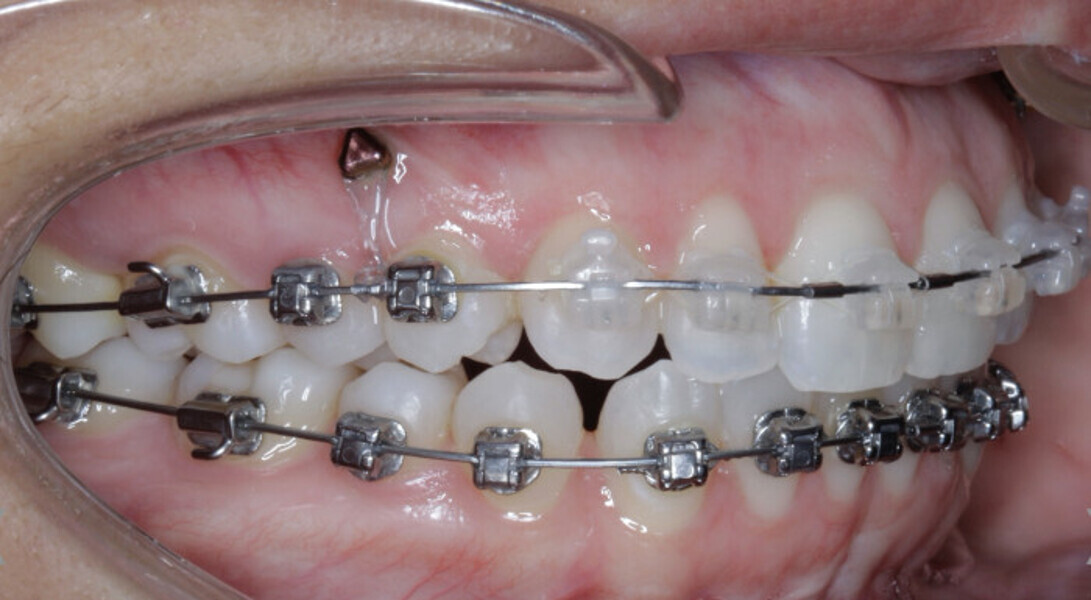

New Age orthodontics and orthopaedics with temporary anchorage devices